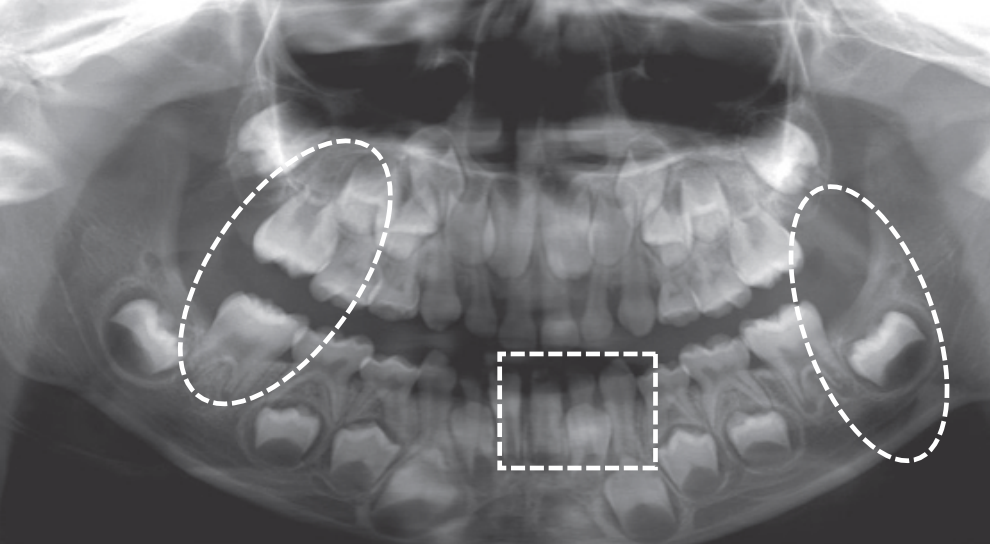

At age 6 is characterized by the erupted first molar in the maxilla, and the erupted central incisor and first molar in the mandible. Teeth erupted – Maxilla ABCDE6, Mandible 1BCDE6 - Teeth unerupted – Maxilla 123457, Mandible 23457

Dental age 7 is characterized eruption of permanent teeth Mandibular Lateral Incisor, Maxillary Central Incisor

Dental age 8 is characterized by eruption of the maxillary lateral incisors

Teeth erupted – Maxilla 12CDE6, Mandible 12CDE6

Teeth unerupted – Maxilla 3457, Mandible 3457